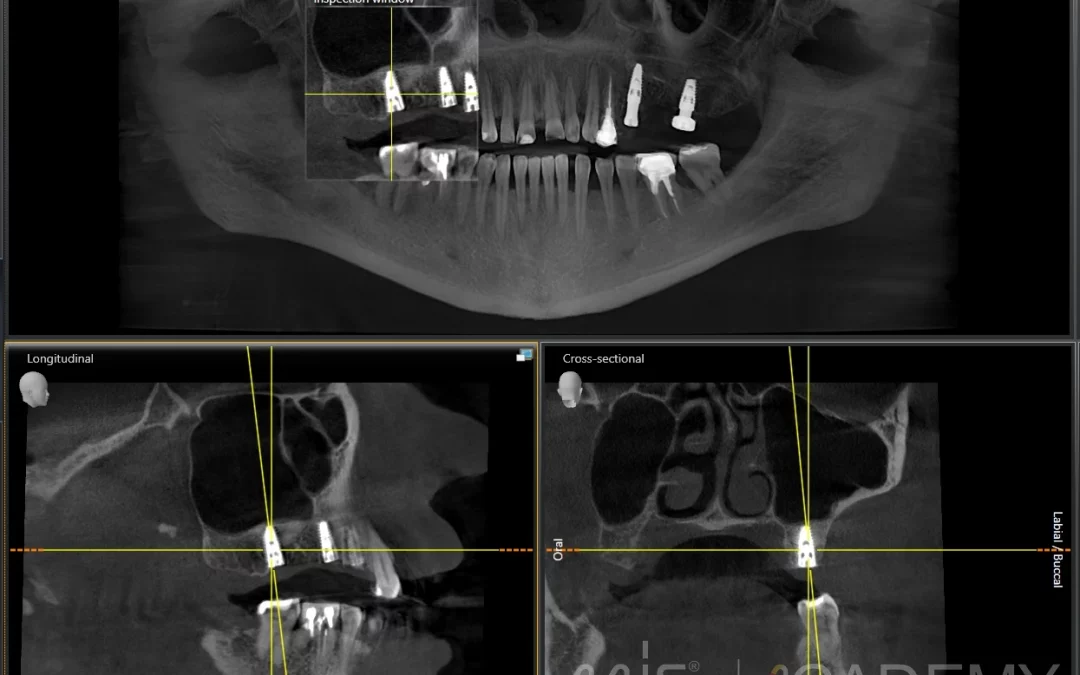

ПЛАНИРОВАНИЕ ИМПЛАНТАЦИИ

Планирование имплантации и дизайн шаблона MGuide в Msoft Пациент 21 год. Ортодонтическое лечение закончил в 16 лет. В этот период пользовался частичный съемным протезом. - Планирование имплантации и дизайн...